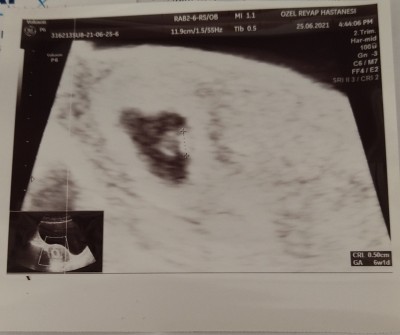

Arkadaşlar ramzi teorisine bakıp doğru çıkan var mı merak ettim. İnternette%70 %90 oranında doğru çıktığı yazıyor ama?

Teoriye göre, kromozomların farklı yöne gitmesi ile plasentanın hangi durumda olduğu belirlenir. Yani plasentanın bulunduğu konum bebeğin cinsiyetini vermektedir.

Plasenta rahmin sağında ise erkek, solunda ise kız bebek olacağı anlamına gelir. Bu da demek oluyor ki;

Plasenta ultrasonda sağ tarafta belirdi ise embriyo XY kromozomlarına sahip olur. Yani bebek erkek olacak demektir.

Plasenta sol tarafta beliriyorsa XX kromozomuna sahip olur. Bu da kız bebek anlamına gelir.

Buna göre benim bebeğim erkek olacak. ?

Gebelik haftası 6

Bu ultrason fotoğrafım 7 hafta 4 günlük ramiz teorisine göre kız mı erkek mi bilen var mı yarın da 11 haftalık olacağım